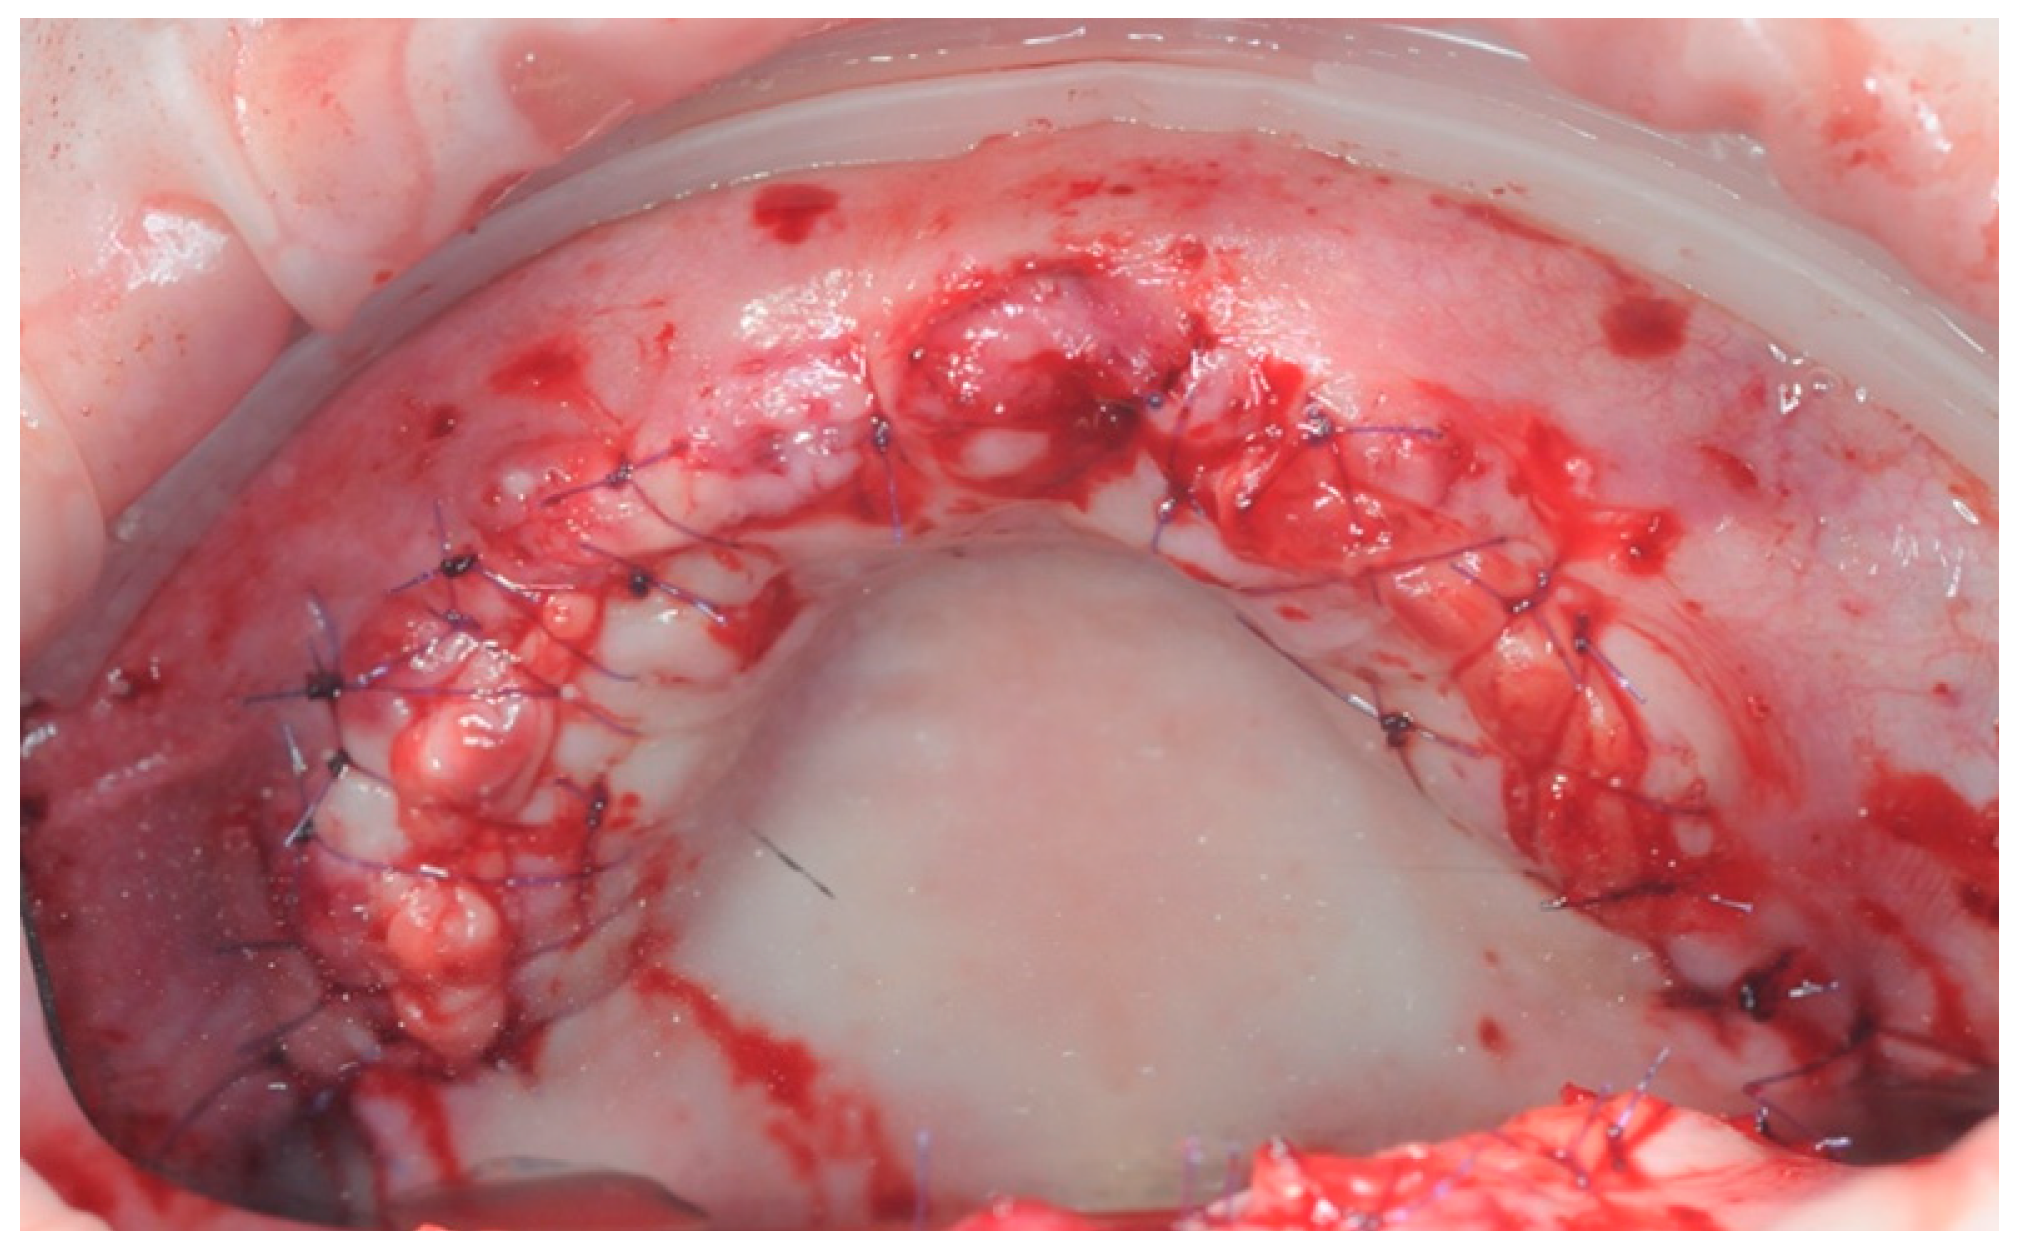

2.3. Re-Entry Surgery